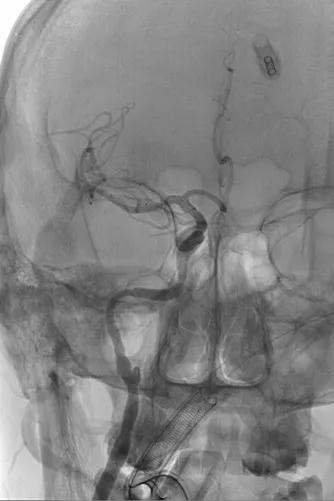

患者信息:

女,59y,因“间断头晕3月余”来院。

患者3个月前无明显诱因出现头晕,持续几分钟可自行缓解。外院行头颅CTA示,右侧颈内动脉巨大动脉瘤。

全麻,卧位,常规消毒铺巾,Seldinger’s穿刺右侧股动脉,置入6F 90cm长鞘。以多功能管导引6F Navien导引导管,尾部连接Y阀1个,三通2个,压力袋1个(肝素盐水),导引导管引领下上行。

全脑血管造影可见右侧颈内动脉海绵窦巨大动脉瘤,瘤体最大径:14.72mm,瘤颈宽:9.12mm。

Synchro 14导丝顺利送支架导管入右侧中动脉下干远端,尾部连接Y阀1个,压力带1个;经支架导管,置入Tubridge® 4.5×35mm,定位良好,顺利释放。

复查造影显示,动脉瘤内造影剂滞留明显,各血管及分支通畅,流速正常。手术结束。